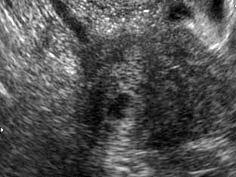

问题 27岁孕妇,孕8周时阴道出现无痛性出血, 血B-HCG为2200ul/ml,根据下图所示,最有可能诊断为 ( )

选项 A、子宫内膜异位症 B、子宫内膜息肉 C、输卵管壶腹部妊娠 D、子宫角妊娠 E、子宫肌瘤

答案 D